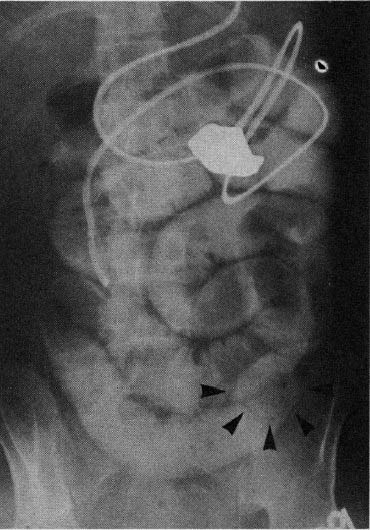

図2. 法廷の様子.中央のまるい囲みの中が被告George Orme,その左がOrme夫人.

【要旨】1896年7月,ニューヨーク州Chemung郡で,帰宅した老紳士George Ormeは妻と下宿人James Punzoの浮気現場に出くわし,拳銃を2発発射した.妻は軽症であったが,間男のPunzoは後頭部に銃弾を受け,意識不明となった.その後,搬送先の病院で外科的に銃弾探索を行ない銃弾は発見できなかったが,2週間後には普通に話したり散歩できるまでに回復した.そこで再度,X線を使用した銃弾探索を行なったが,銃弾はうつらず失敗におわった.X線検査は,Crookes管を後頭部から1.5インチの距離に置き,約30分曝射した.その数時間後,患者は発熱し,意識が低下して20日後に死亡した.剖検では,後頭葉の深さ1.5インチの位置に銃弾が発見されたが,その周囲には良好な治癒過程が見られた.

Ormeは殺人罪で起訴されたが,弁護側は死因は銃創ではなく,X線検査であると主張した.著者のPitkinは被告側証人として出廷し,X線照射は組織に有害であり,外傷で刺激状態にある脳に対して,なんら防護を行なわない状態で照射したことが死因であると証言した.この結果,被告は無罪となった(図2).